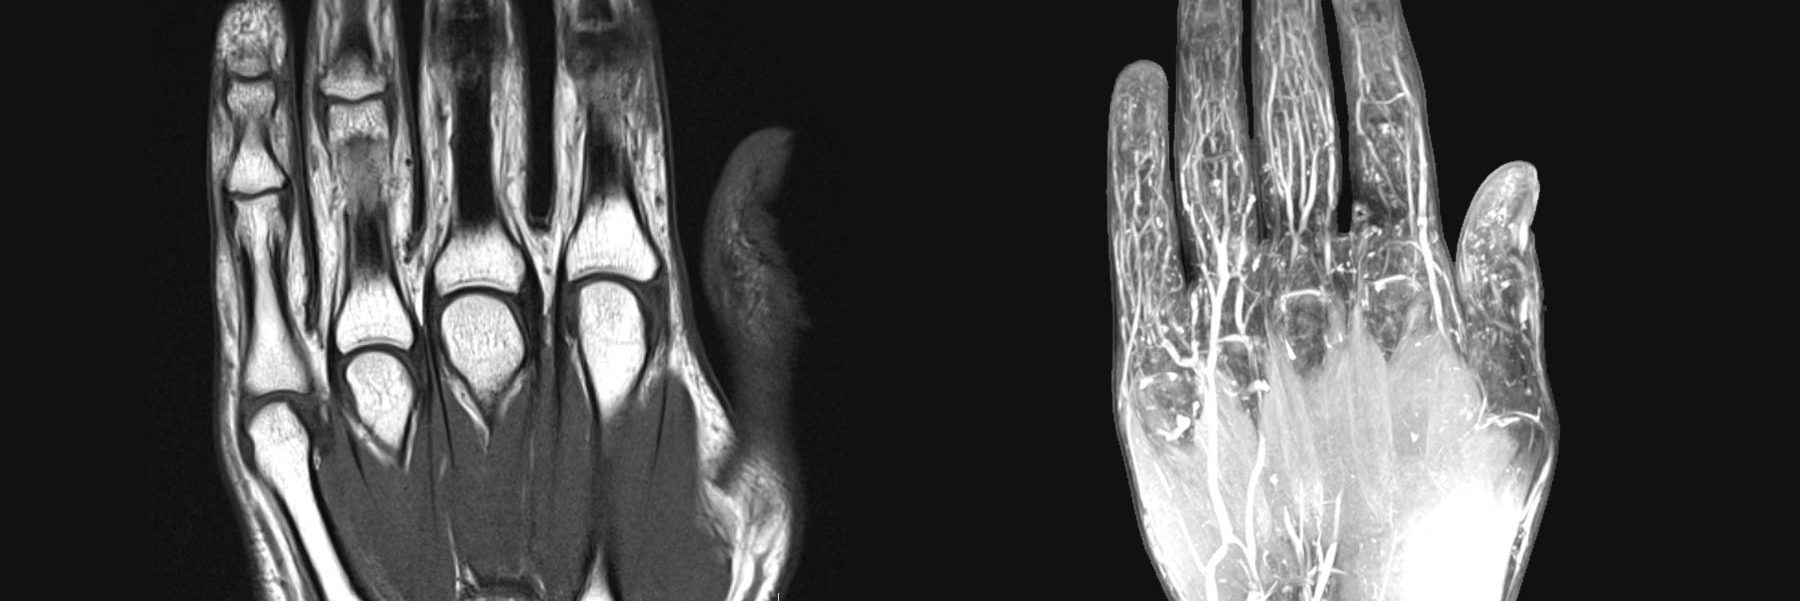

Nuestras manos son herramientas fundamentales en el día a día. Las usamos constantemente para trabajar, realizar tareas cotidianas e incluso comunicarnos.

Cuando aparece una lesión o enfermedad que afecta su movilidad o provoca dolor, nuestra calidad de vida se ve seriamente afectada.

Afortunadamente, la cirugía de la mano permite solucionar muchos de estos problemas, restaurando la funcionalidad y eliminando las molestias. A continuación, te explicamos cuáles son las intervenciones más comunes y en qué casos pueden ser necesarias.

Además de tratar las patologías frecuentes, la cirugía de la mano tiene un papel fundamental en la reconstrucción funcional y estética tras traumatismos, cirugías previas o enfermedades neurológicas.

Cada caso requiere una valoración individualizada por un especialista en cirugía de la mano, ya que la elección del tratamiento depende del tipo de lesión, la funcionalidad previa y los objetivos del paciente. El objetivo final es restaurar el movimiento, aliviar el dolor y recuperar la autonomía de la mano.